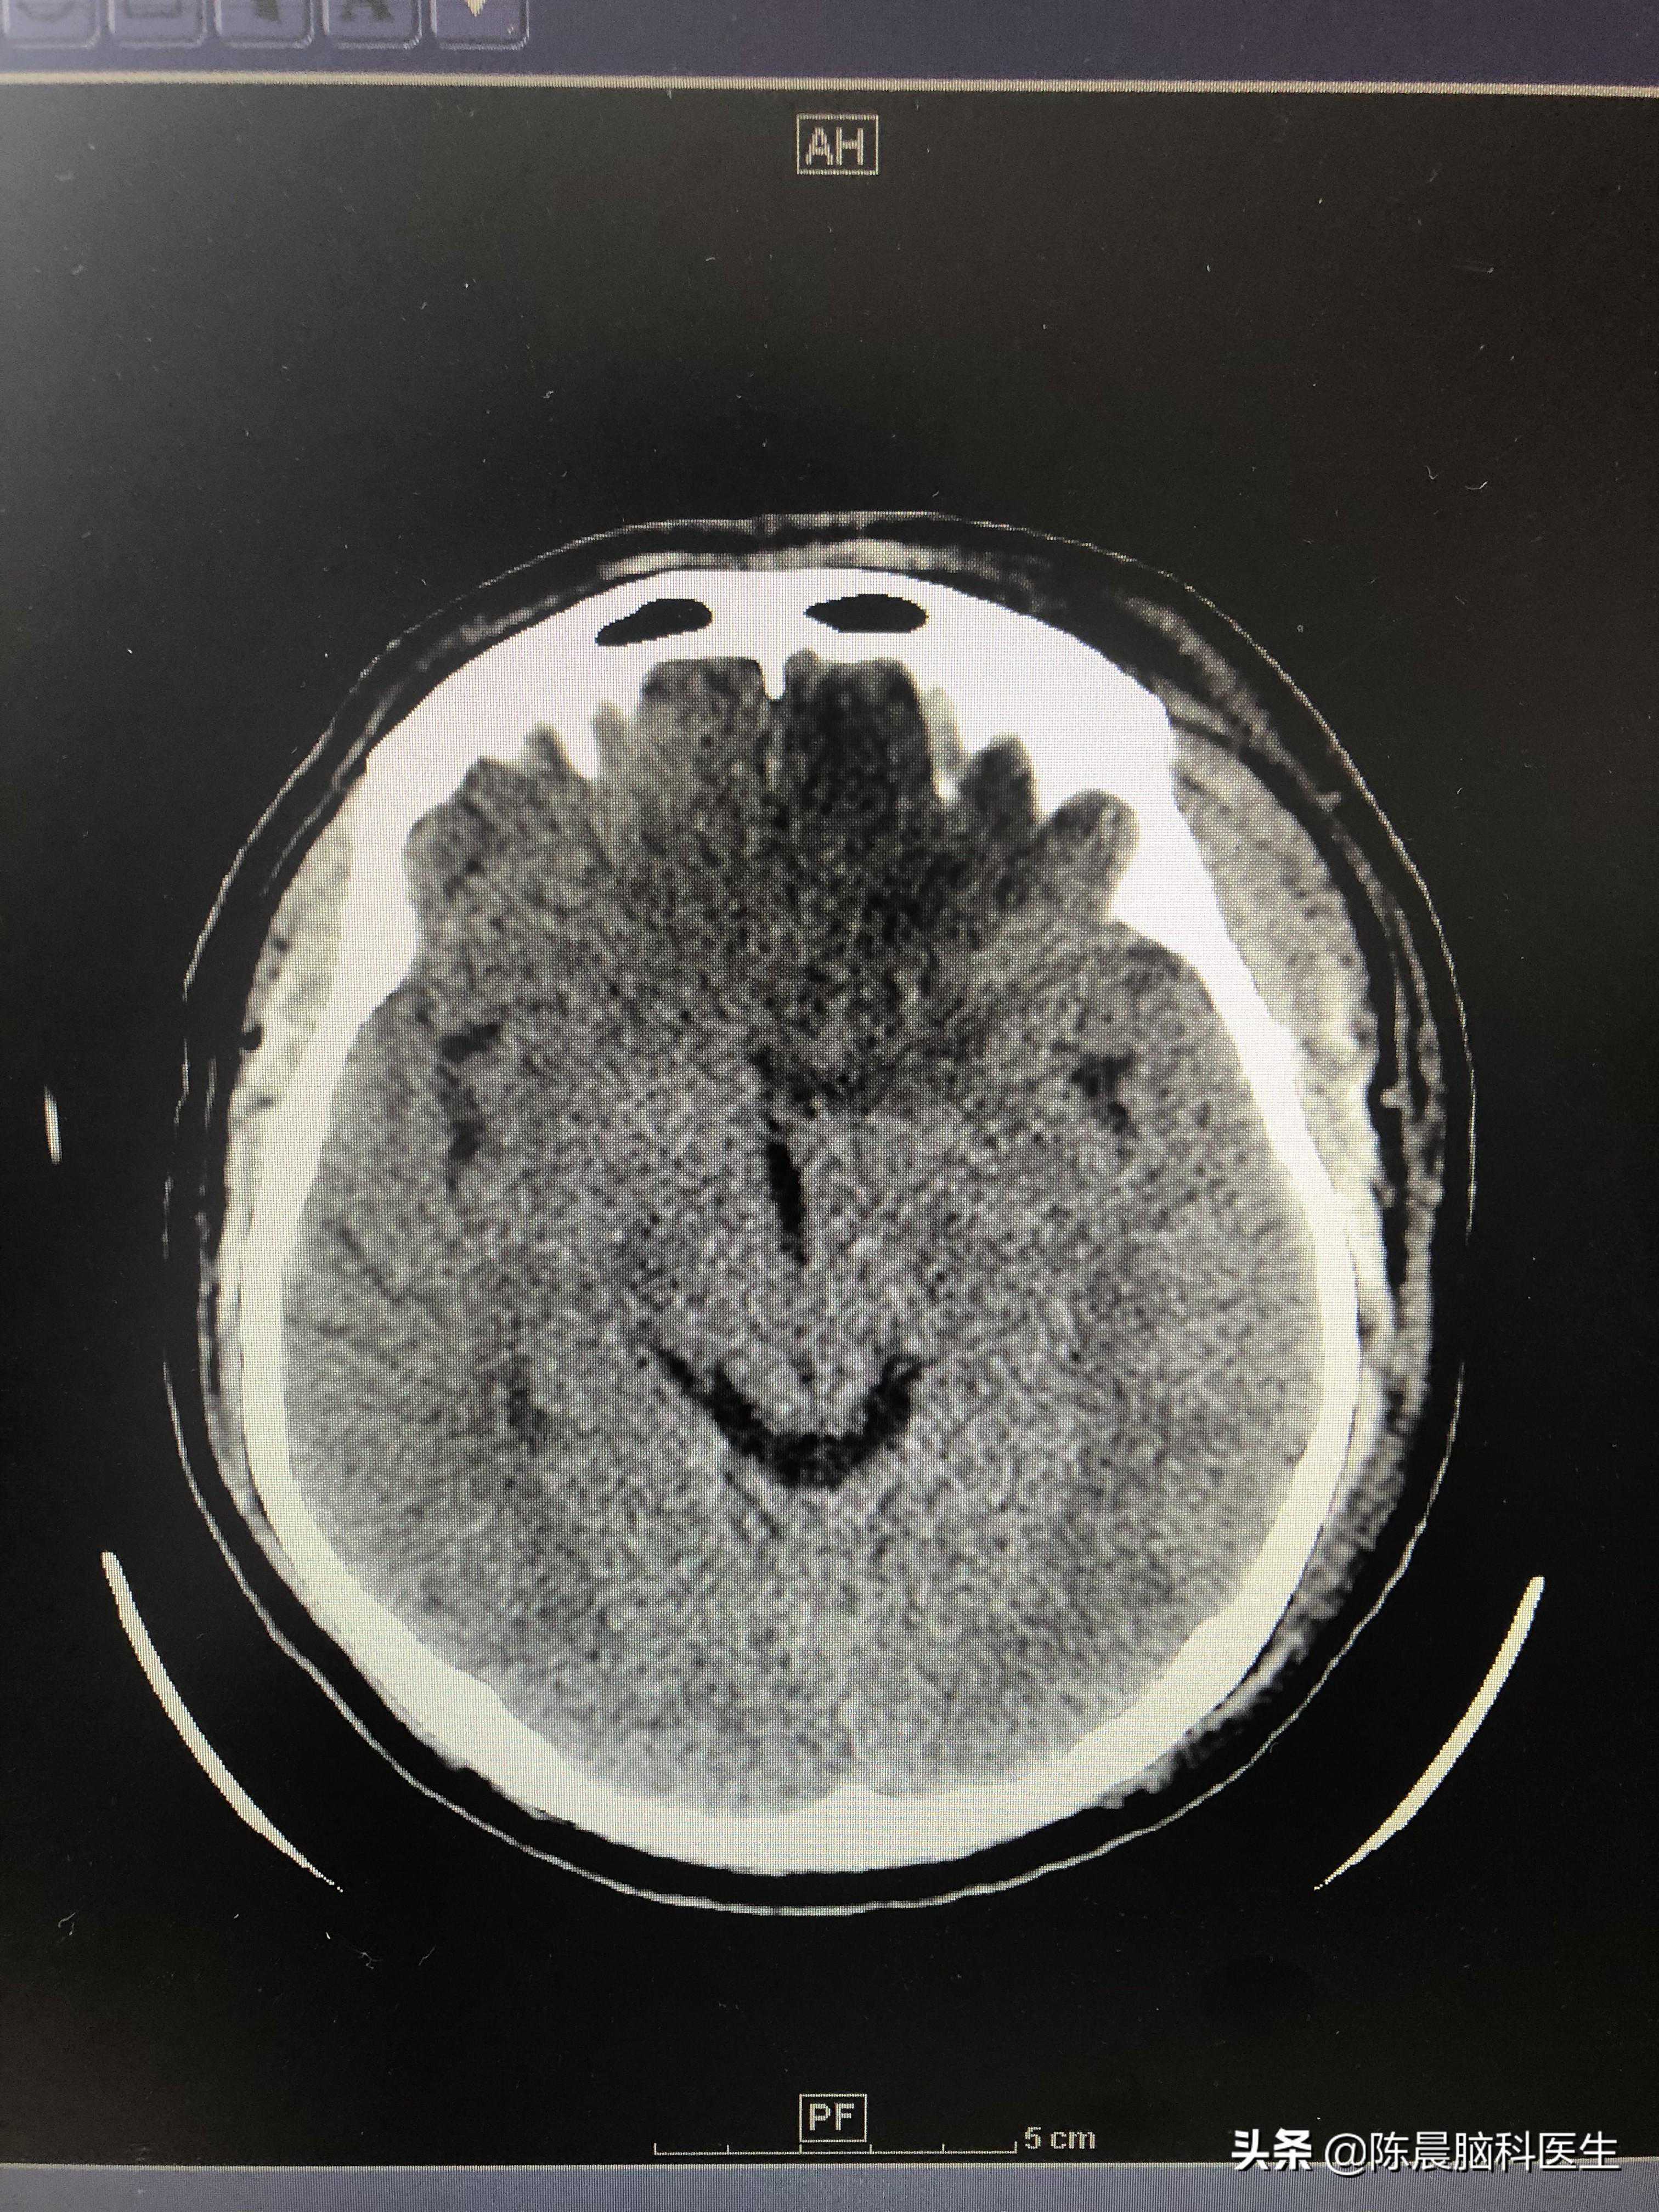

现在恢复的还算不错,四肢活动灵活,说话清楚,思维清晰,准备出院了。可以设想,当时如果他在家再拖一会儿,或者先去了没有救治能力的医院。有可能颅内出血会持续增多,直到挂在墙上!

出血已经全部吸收

针对我这个朋友,他肢体功能和语言功能没有受损真是万幸。毕竟是优势半球的大量脑出血,而且当时开颅后额叶毁损,进行了部分的脑叶切除,但目前看对于主要功能竟然没有影响。后续主要看看会不会继发癫痫了,毕竟脑叶的损伤继发癫痫的非常多,需要定期复查。